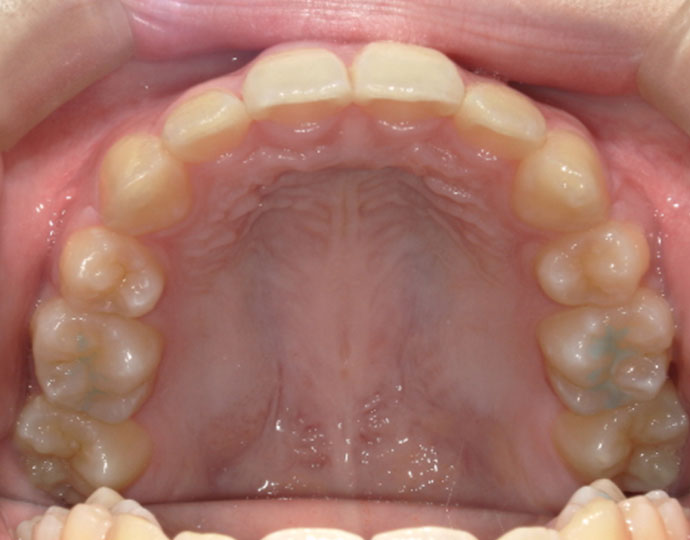

治療後

| 診断 | 叢生歯列不正咬合 |

| 治療方針 | 上下顎左右第一小臼歯の抜歯(計4歯) |

| 治療に使用した装置 | セルフライゲーションブラケット(インタラクティブタイプ) |